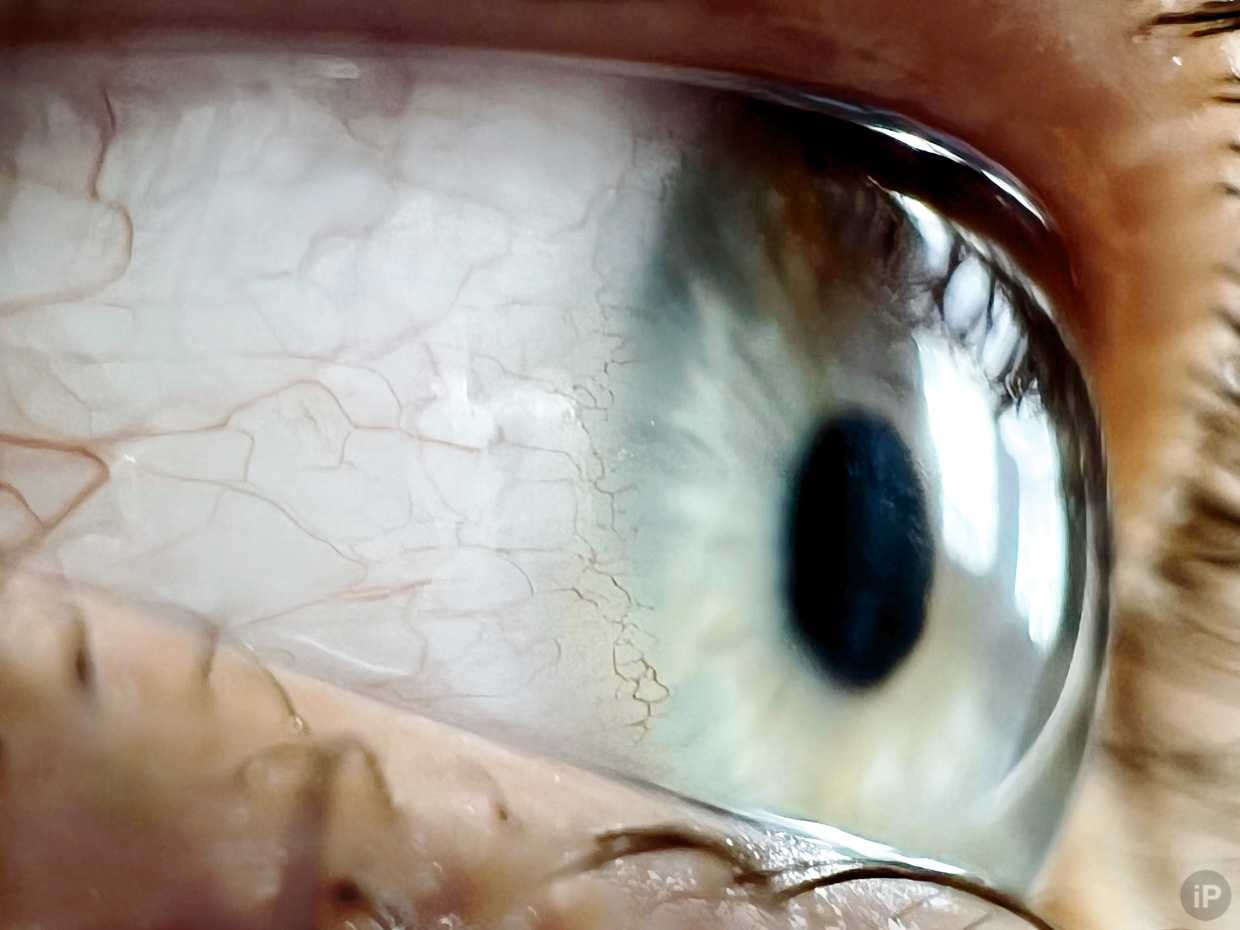

Снимать самого себя неудобно

Для первого эксперимента выбрал собственные глаза, но получилась криво. Даже от дублирования экрана на Apple Watch толка не было, потому что качество предпросмотра недостаточно для точной фокусировки. Но что-то получалось. Фото выше показало возможности модуля и дало добро на дальнейшие эксперименты.

Делал и более удачные снимки, но тут чётко видно сосуды вокруг роговицы, которых быть не должно. Они настолько маленькие, что в зеркале ни разу их не замечал.

Благодаря камере iPhone 13 Pro я вживую убедился, что моим глазам поступало недостаточно воздуха при использовании гидрогелевых контактных линз. Если кому-то интересно, почитайте о том, как этого избежать. Если коротко, носите силикон-гидрогелевые.